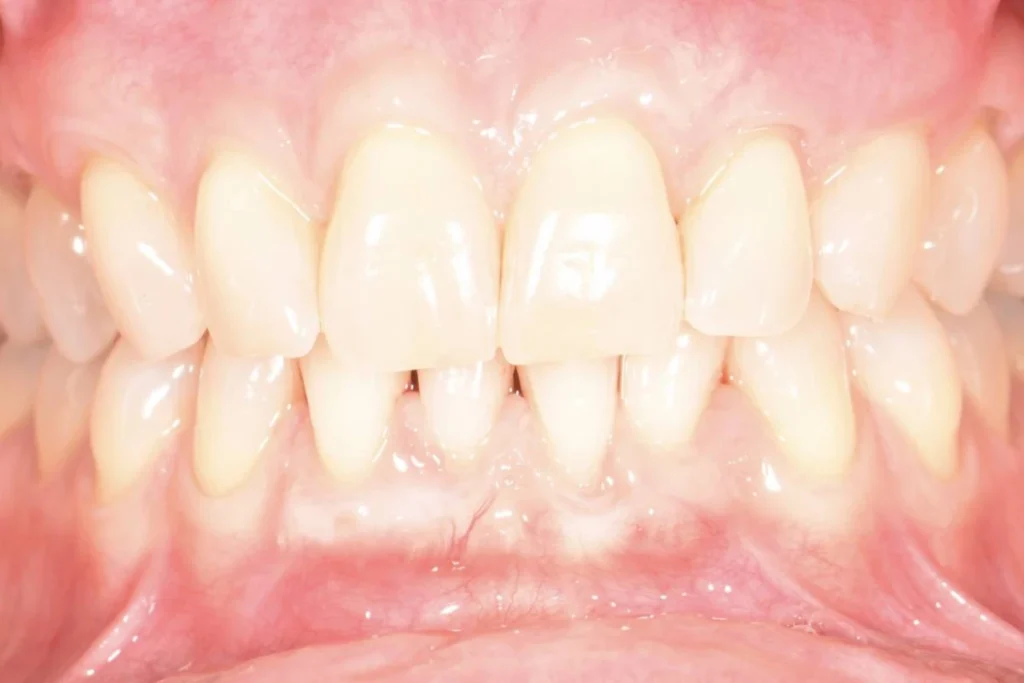

Le sourire c’est bien sûr les dents, leurs formes, leur alignement, leur teinte mais c’est aussi l’harmonie qui réside entre le « blanc » et le « rose ». Cet équilibre peut être perturbé par un déchaussement des dents entrainant une impression de « dents longues ».

Le fait d’avoir les gencives qui se rétractent laissant apparaitre les racines des dents est appelé Récessions Gingivales.

Très souvent, ces récessions sont d’origine traumatique, dues à un brossage exercé avec une pression excessive et/ou avec une brosse à dents trop dure.

La thérapeutique mise en oeuvre pour rétablir la balance entre la gencive et les dents s’appelle la greffe de recouvrement gingival.